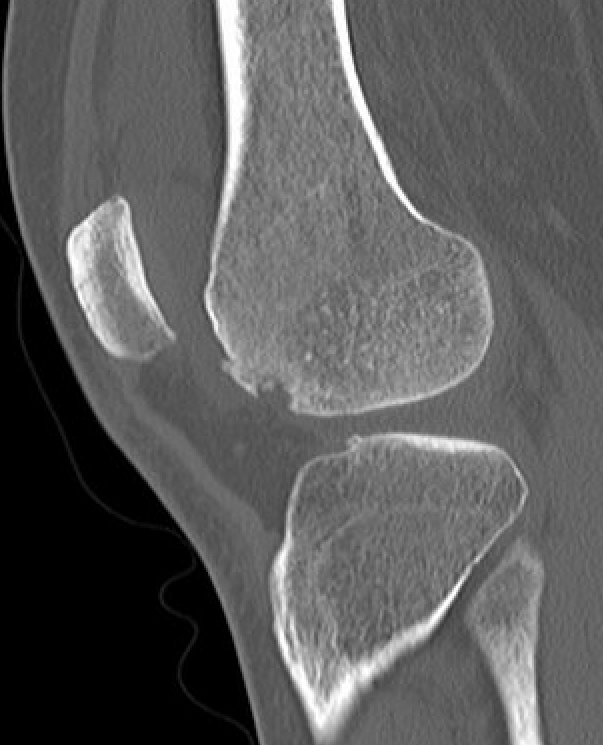

CT

Osteochondral fracture of the lateral femoral condyle

Large osteochondral fracture medial facet patella

Large osteochondral fracture lateral femoral condyle